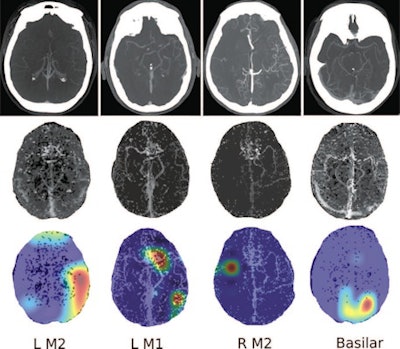

Four separate patients with large-vessel occlusions correctly predicted by the algorithm. The top row shows a representative CT slice from the delayed venous-phase CT angiography scans. The middle row shows the preprocessed maximum intensity projection images that function as the input to the model. The bottom row are overlaid heat maps, with areas in red showing the most discriminative regions. These so-called hot regions correlate with the occlusion location (respectively: left [L] M2, L M1, right [R] M2, basilar) in each patient. Images and caption courtesy of the RSNA.The researchers found that using combinations of phases -- and especially all of the phases -- led to a higher AUC for detecting LVO stroke than single-phase CTA. The additive effect from combining additional delayed phases with phase 1 indicated that findings of both initial absence of opacification and delayed enhancement were important factors in producing better algorithm performance, according to the researchers.